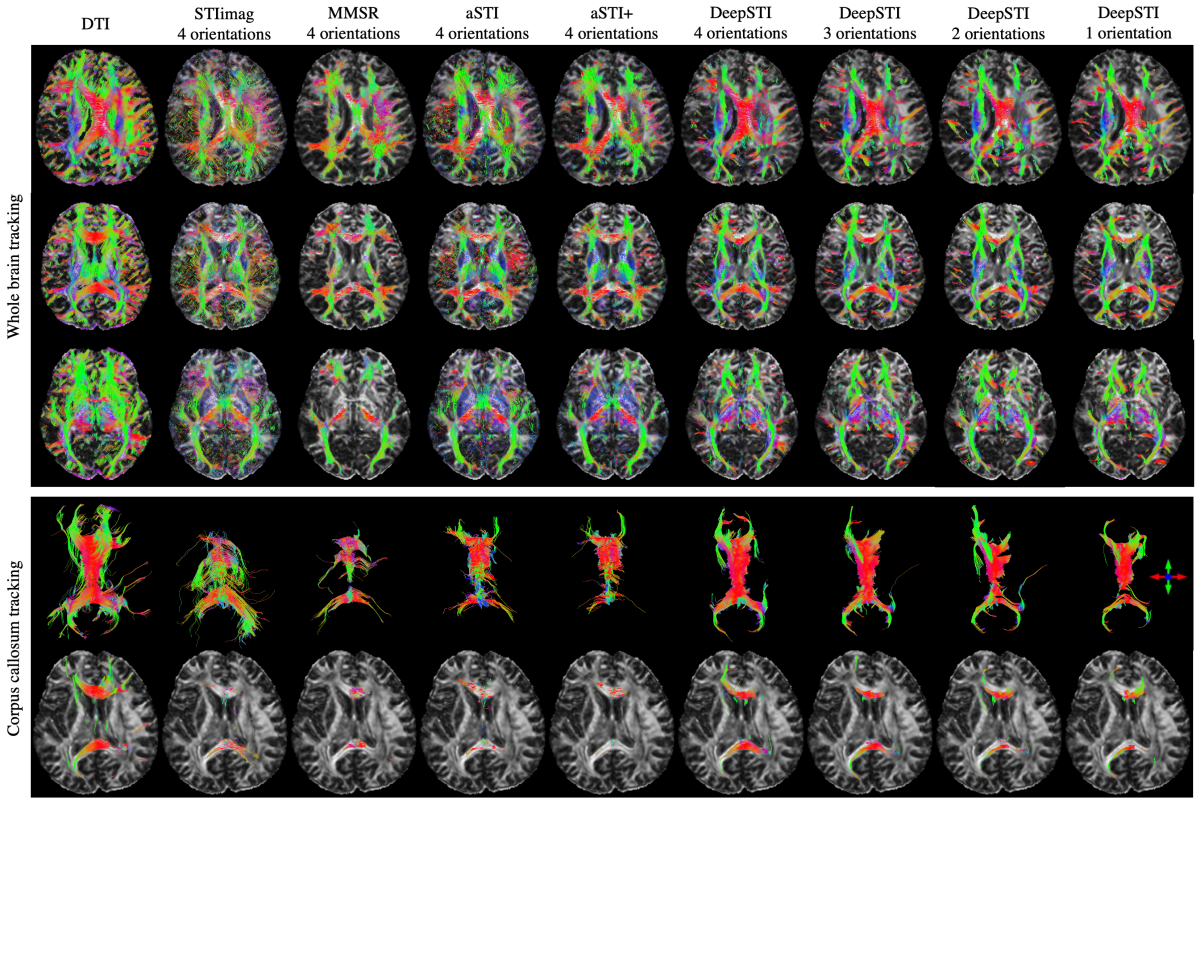

Refer to caption

Figure 5: STI-based Fiber tractography results from phase measurements for a subject at 7T with 0.98×\times0.98×1(mm)3absent1superscript𝑚𝑚3\times 1(mm)^{3} resolution. Rows 1-3: whole brain tracking results overlaid on a DTI-based FA map at different axial planes. Row 4: 3D volume rendering of neural fibers passing corpus callosum. Row 5: 2D visualization of neural fibers passing corpus callosum. Columns from left to right: DTI, STIimag’s result from 4 orientations, MMSR’s result from 4 orientations, aSTI’s result from 4 orientations, aSTI+’s result from 4 orientations, DeepSTI’s results from 4, 3, 2 and 1 orientations. No FA or MSA weighting is used in visualizing the tractography results.

Figure 5 depicts fiber tracking results achieved by different methods using in vivo data acquired at 7T with 0.98×\times0.98×\times1 mm resolution. With 4 head orientations, DeepSTI provides more complete fiber reconstructions as compared to other STI methods. Even with fewer head orientations, DeepSTI can still recover a good portion of major fiber pathways in whole brain tracking (top row of Fig. 5). Notably, the fibers passing through CC connecting the left and right hemispheres can still be nicely recovered even from only one head orientation (middle and bottom rows of Fig. 5). Results for a 3T subject are included in the Appendix (Fig. 11).